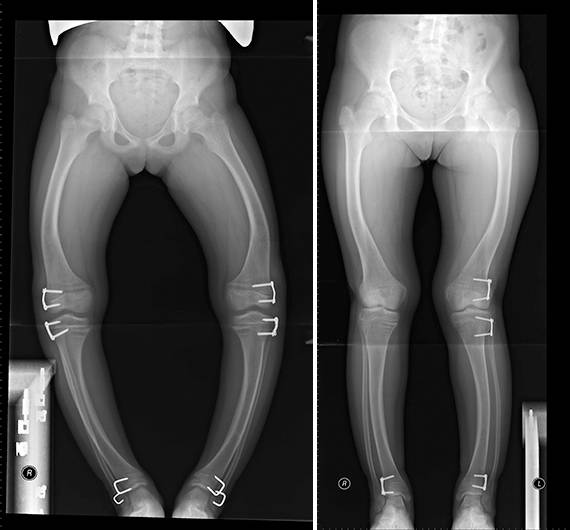

Где сделать рентген нижних конечностей (ТБ, коленный, голеностоп) в одном снимке? Посоветуйте, пожалуйста!

Девочки, где в городе можно сделать ренген нижних конечностей, в одном снимке все суставы (ТБ, коленный, голеностоп), кроме Екатерининской?

Рекомендовал ортопед, чтобы исключить патологию.